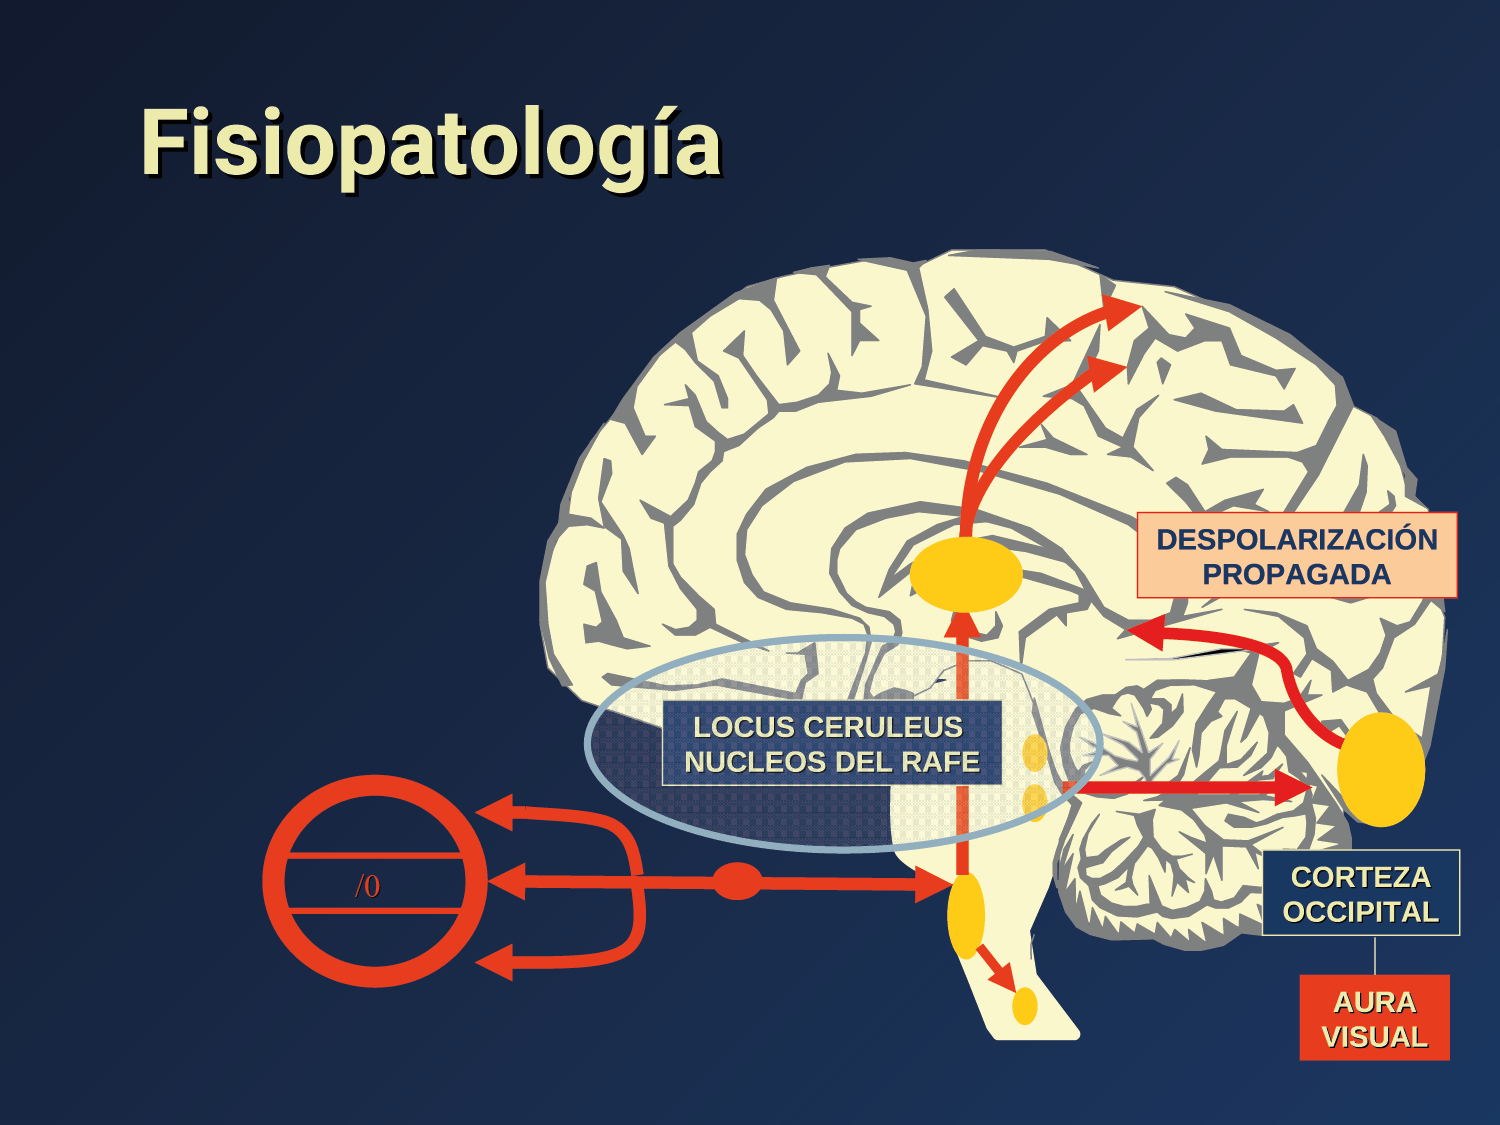

El aura de la migraña, al menos en su sentido clásico, tiene relación con la depresión cortical que se propaga por la corteza cerebral y participa como un actor paralelo cuando se producen las crisis. (Figura 2)

Se cree que una onda transitoria de despolarización neuronal de la corteza (Figura 9), la depresión de propagación cortical (CSD), es el mecanismo cerebral fisiopatológico subyacente al fenómeno clínico del aura de la migraña. Leão(21) estableció un mecanismo subyacente hipotético. Luego de haber estimulado eléctricamente la corteza de conejo y encontrar una depresión EEG que se propagaba a una velocidad similar de 3 mm/min centrífugamente desde el sitio de estimulación sugirió que podría ser la base del aura migrañosa. Esta hipótesis está fundamentada en la correlación entre las características neurofisiológicas de una CSD, su propagación retinotópica en la corteza visual y las características y dinámicas de los déficits visuales(14, 15) y en las observaciones indirectas derivadas de los estudios de imágenes que respaldan aún más este concepto(16) Sin embargo, sobre la base de la comprensión actual de la migraña, es poco probable que la CSD esté involucrada en el inicio del síndrome completo de la migraña(17).